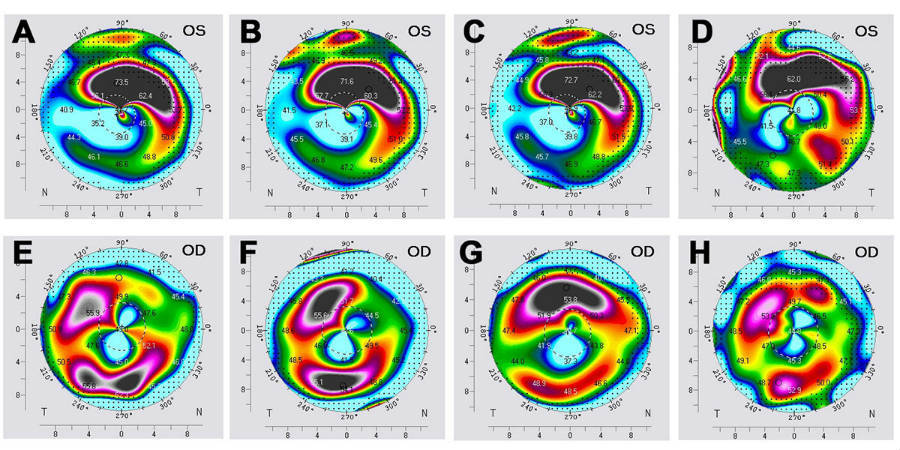

“We only treated two eyes, but it was the first time a Terrien could be stopped and partially reversed,” Farhad Hafezi, MD, PhD, OSN Europe Edition Board Member, said in a telephone interview with Ocular Surgery News